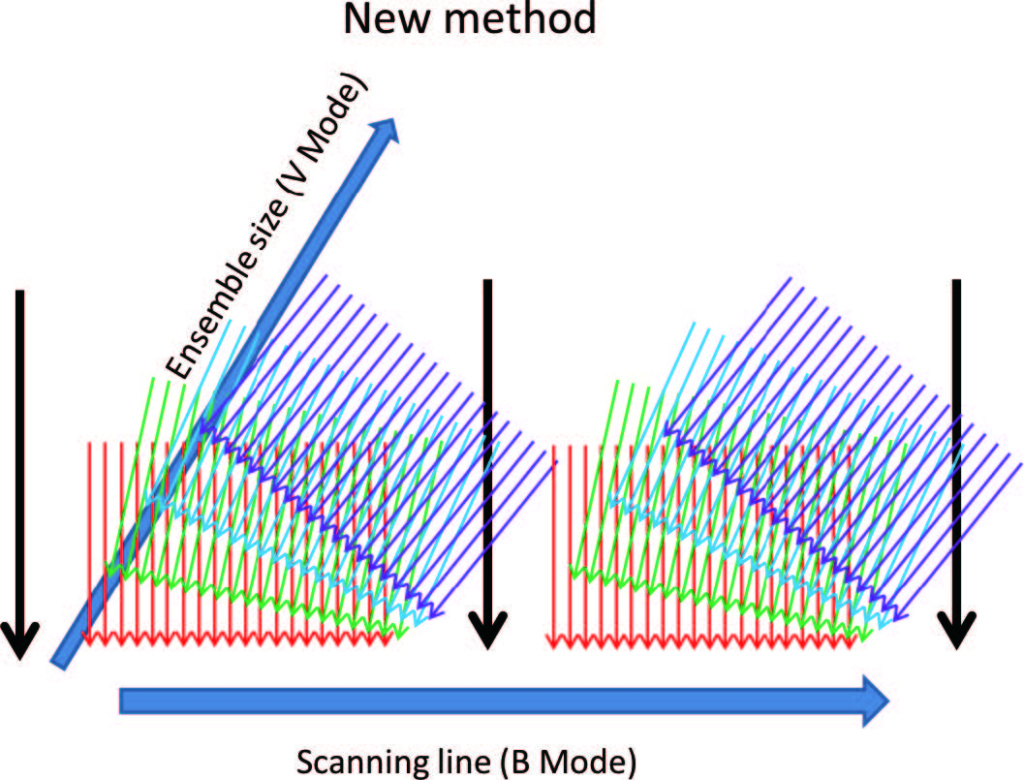

Благодаря кардинально иному принципу формирования ультразвуковых кадров (технология зонного сканирования ZST+) и высокой аппаратной мощности прибора Mindray Resona 7 при однократном цикле приема-передачи сигнала может быть получено несколько строк изображения. Поскольку полученные строки отражают информацию о скорости частиц крови в один временной период, то исчезает необходимость программной синхронизации данных, что позволяет применять фильтрацию данных в режиме реального времени для удаления помех.

Для того чтобы получить направленный вектор скорости кровотока в любой его точке используются множество разнонаправленных циклов приема-передачи эхосигнала (Рисунок 2). Затем скорость (величина вектора скорости) рассчитывается с помощью метода, изображенного на рисунке 3. Благодаря множественному разнонаправленному сканированию, в каждой исследуемой точке кровотока ультразвуковая система получает вектора скорости в плоскости каждой итерации цикла приема-передачи эхосигнала. Истинный вектор скорости вычисляется путем компаундинга и регрессионного анализа полученных данных. Кроме того, поскольку платформа ZST+ хранит дамп оригинального эхосигнала, то он же используется для формирования изображения в B-режиме, что делает возможным как высокочувствительную регистрацию потока, так и высокое разрешение серошкального изображения.